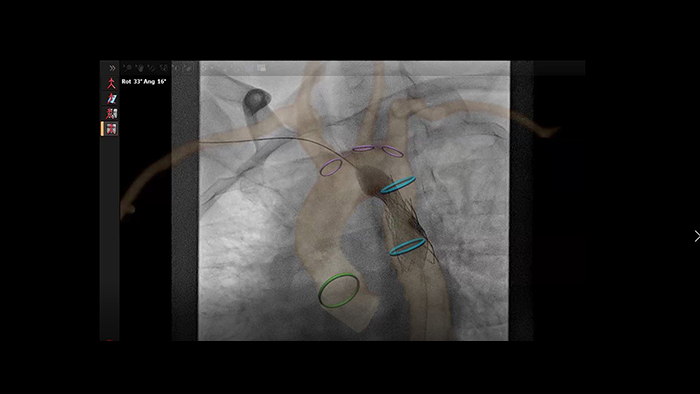

Automatic vessel analysis from rotational angiography with SmartCT

SmartCT live guidance